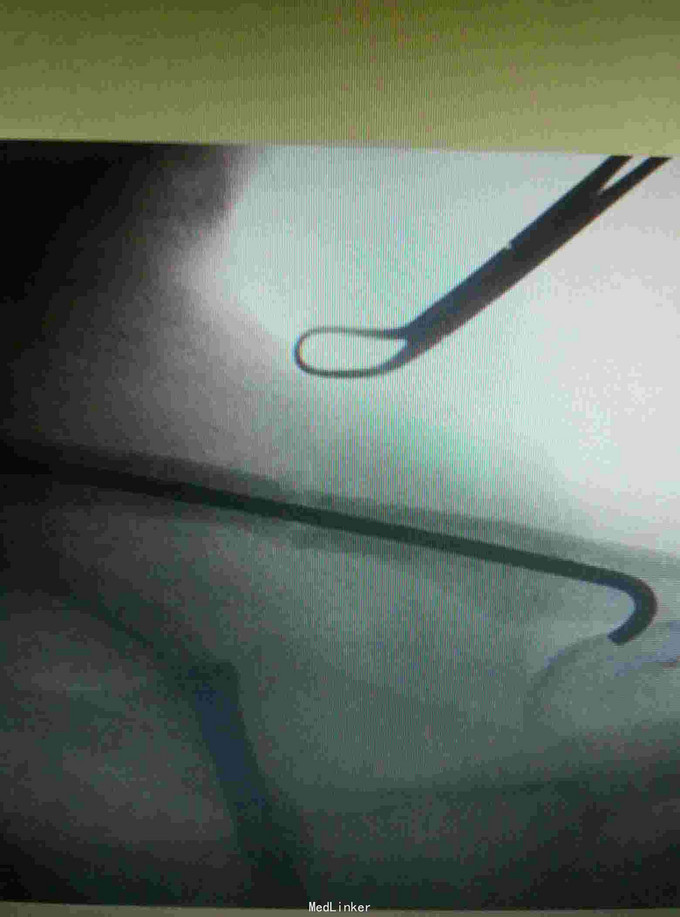

患者,女性,34岁,摔伤左肩部疼痛,活动受限3小时入院

入院查体左锁骨处压痛,畸形,活动受限,入院完善影像学检查,排除肺部,神经损伤。

诊断:左锁骨骨折。 给予行闭合复位钢针固定。